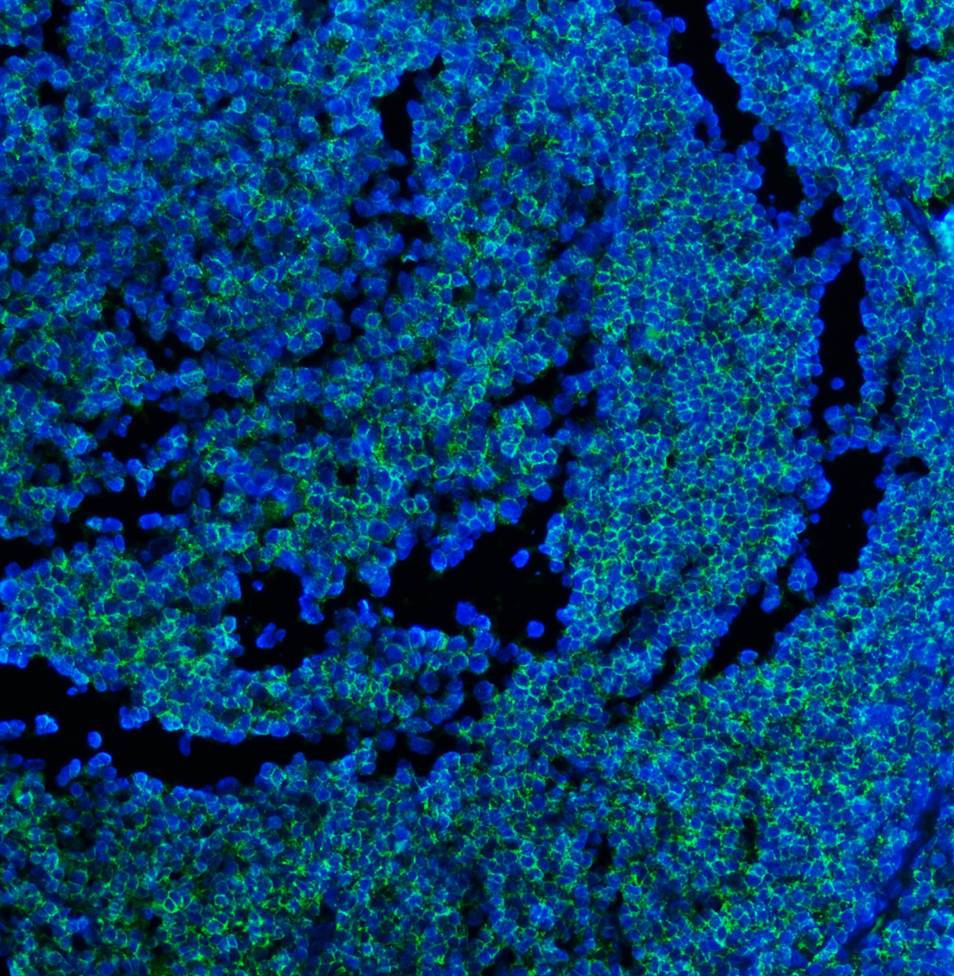

IF analysis using anti- CD45/PTPRC Antibody (M00555-5).detected in paraffin-embedded section of human tonsli tissues. The tissue section were stained using the Fluoro488 conjugated Anti-mouse IgG Secondary Antibody ((green)(Catalog # BA1126) and counterstained with DAPI (blue).